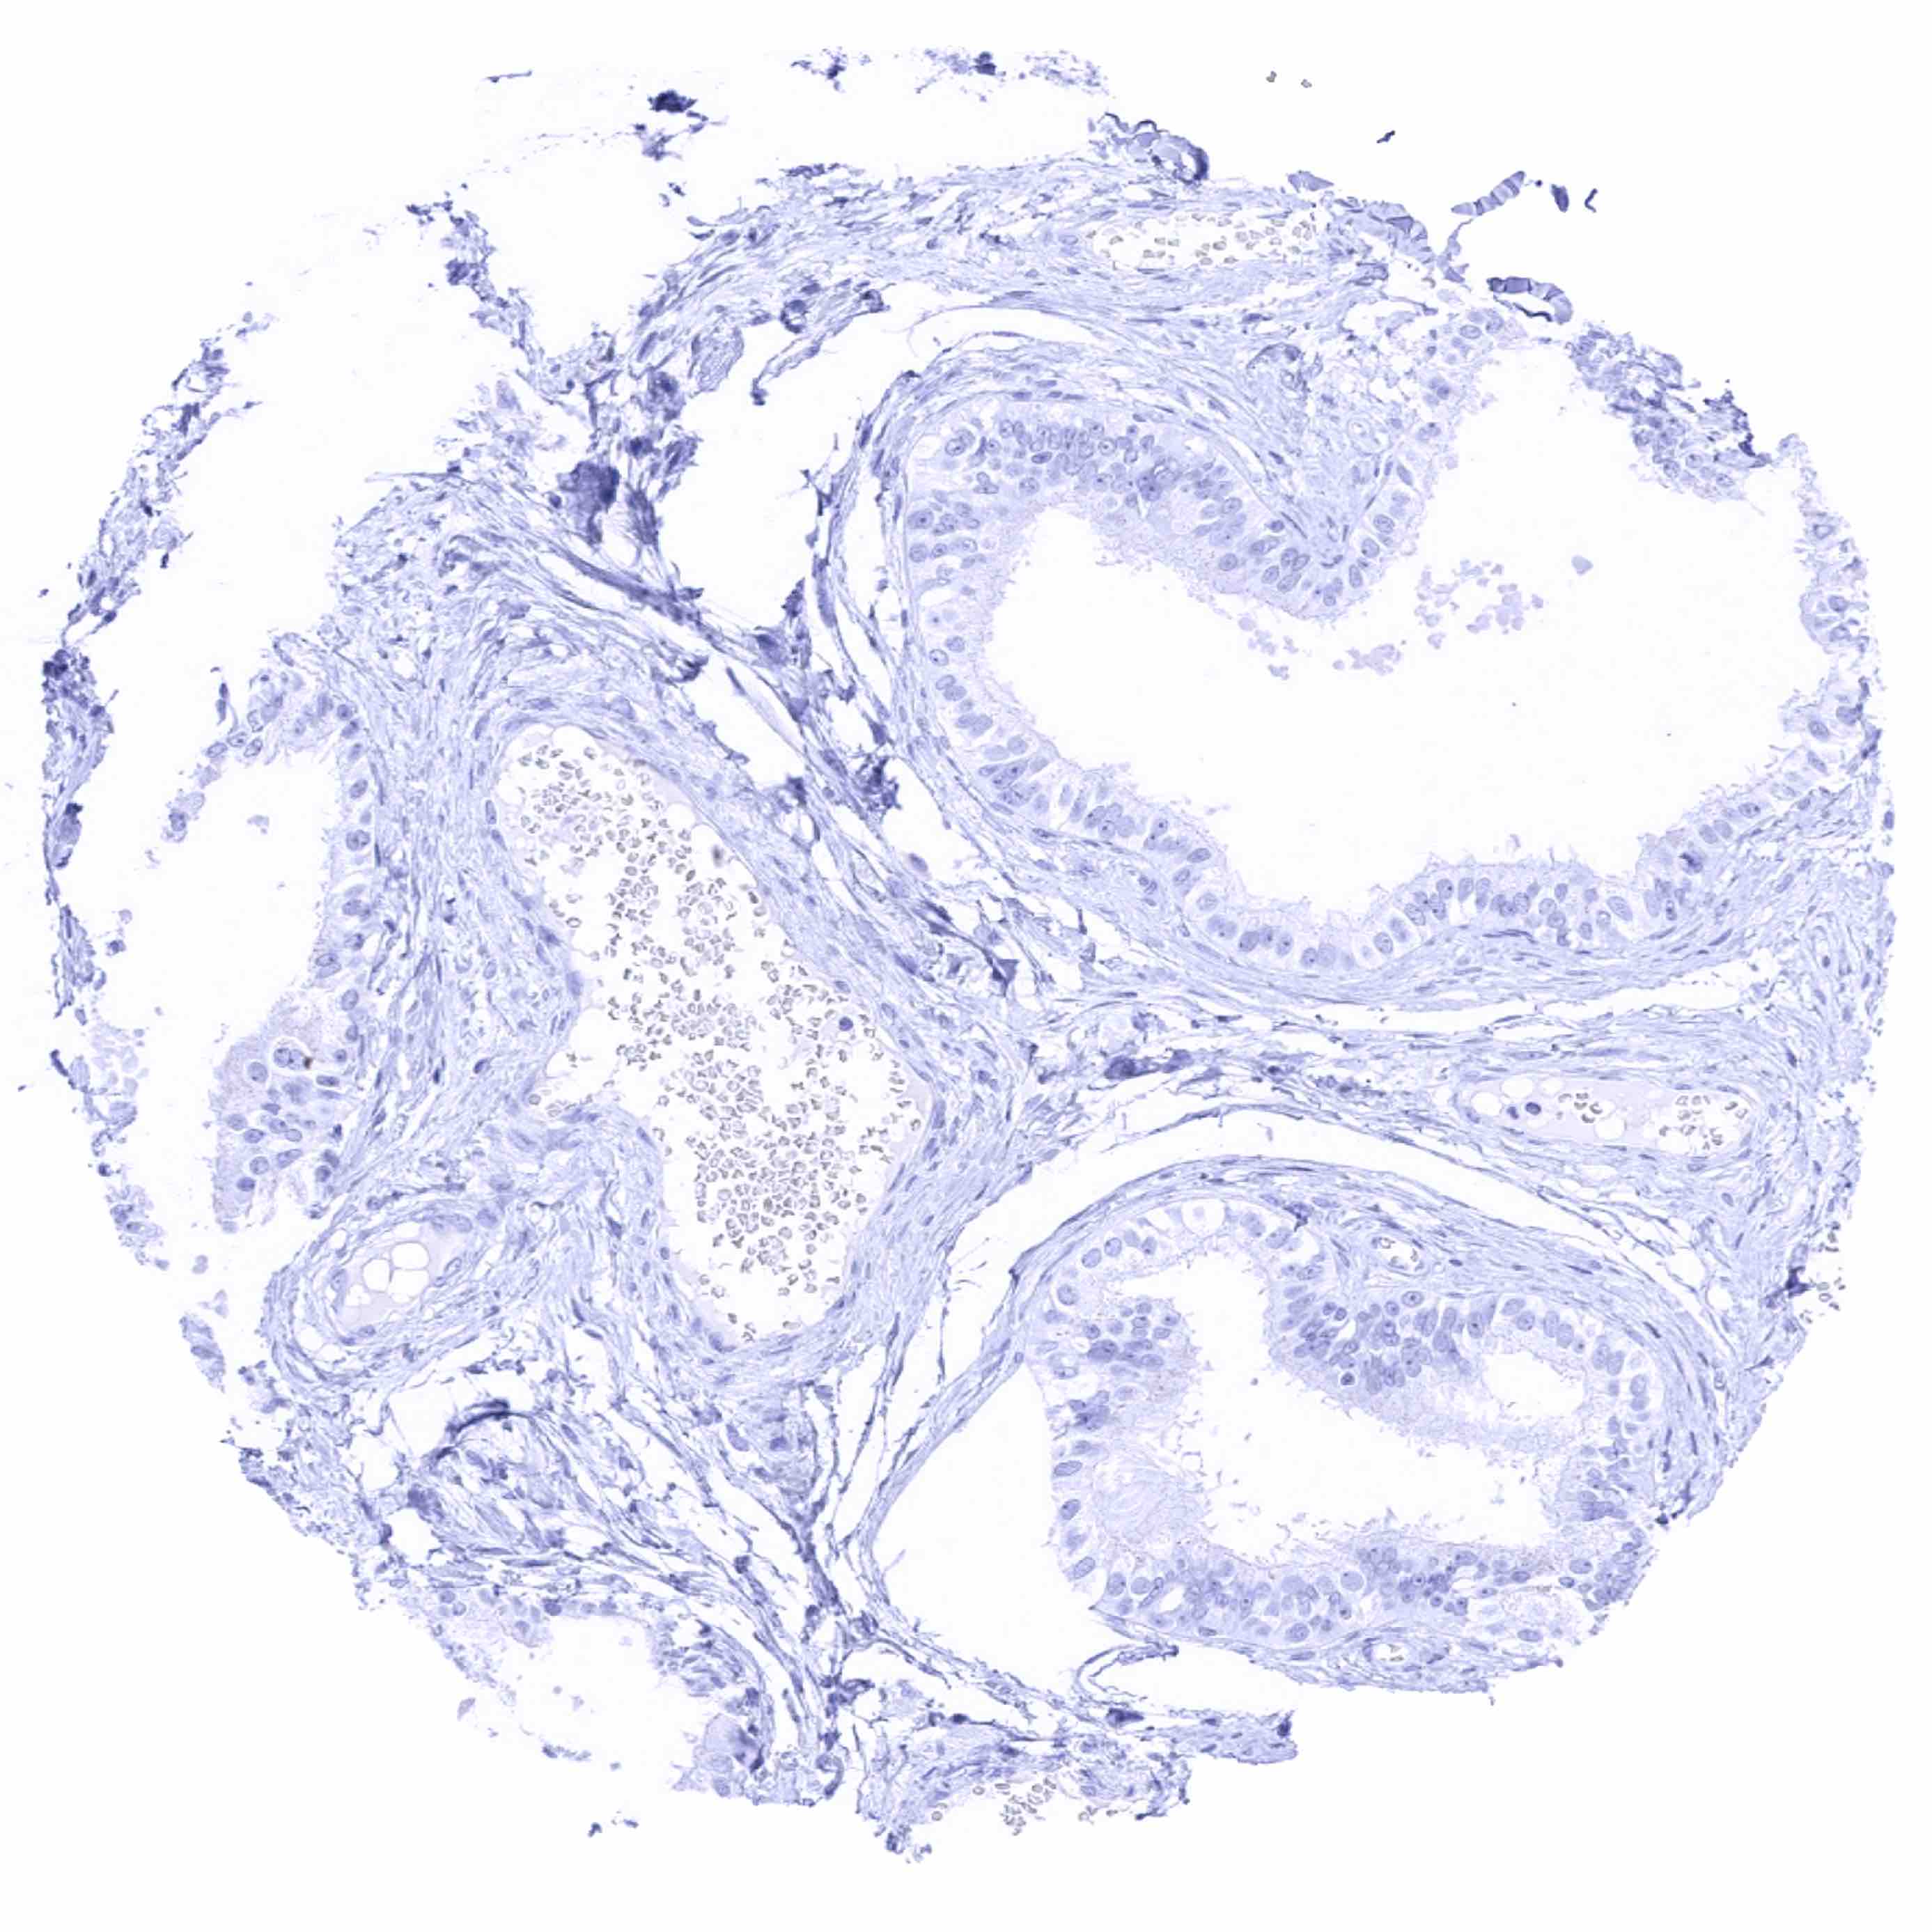

Seminal vesicle

Epididymis (Caput)

Epididymis (Cauda)